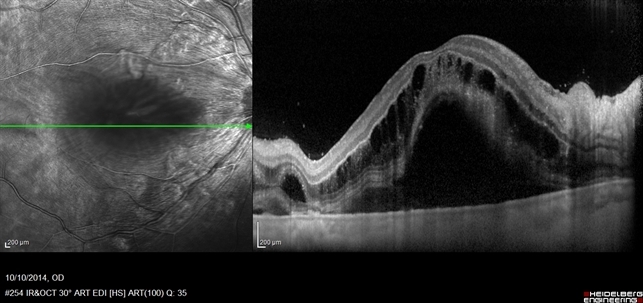

Кистовидный макулярный отек характеризуется образованием микрокист, количество и размер которых постепенно увеличивается. При офтальмоскопии кистовидный отек макулы не всегда хорошо виден. При слабо выраженном отеке исчезает нормальный фовеальный рефлекс, сосуды в макулярной области приподнимаются над пигментным эпителием.

При биомикроскопии, с использованием бесконтактной или контактной линзы, выявляется утолщение сетчатки, мелкие кисты, разделенные нежными перегородками. Следует отметить, что в фовеальной зоне кистовидный отек имеет звездчатую форму (полости радиально расходятся от центральной микрокисты), в пара- и перифовеальной области — он сотовидный. Это обусловлено анатомическим строением сетчатки. Так в фовеа нервные волокна имеют косое, а в пара- и перифовеальной зоне — вертикальное направление. При выраженном кистовидном отеке полости увеличиваются в размерах, сливаются, септы утолщаются, приобретают беловато-серый цвет. В длительно существующих крупных кистах нередко возникает разрыв ее внутренней стенки при сохраненной наружной. В этом случае формируется ламеллярный макулярный разрыв, что клинически проявляется значительным и стойким понижением остроты зрения. При кистовидном отеке макулы, без нарушения целостности внутренней стенки, зрение после купирования основного процесса может частично или полностью восстанавливаться.

Длительное существование кистовидного отека или кистовидной дистрофии макулы иногда ведет к развитию центрального разрыва сетчатки в результате нарушения целостности внутренней и наружной стенок кисты.

Макулярный разрыв имеет характерные офтальмоскопические признаки. Он локализуется в фовеальной зоне и выглядит в виде фокуса розового цвета, с четкими границами, овальной или округлой формы. По краю разрыва обычно располагается зона отслойки нейроэпителия с кистовидно измененной сетчаткой и перераспределенным пигментом. На дне разрыва могут быть видны желтые точечные дистрофические очажки. При гистологическом исследовании выявляется деструкция пигментного эпителия, а также макрофаги с включениями пигмента. С течением времени макулярные разрывы претерпевают изменения. Редко их диаметр уменьшается или остается прежним, чаще — увеличивается, как и отслойка нейроэпителия и кистовидный отек. На дне разрыва величина, форма и число желтых очагов также изменяется. Нередко над макулярным разрывом располагается крышечка несколько меньшего размера, чем сам разрыв.

При макулярном разрыве может определяться частичная или полная задняя отслойка стекловидного тела.